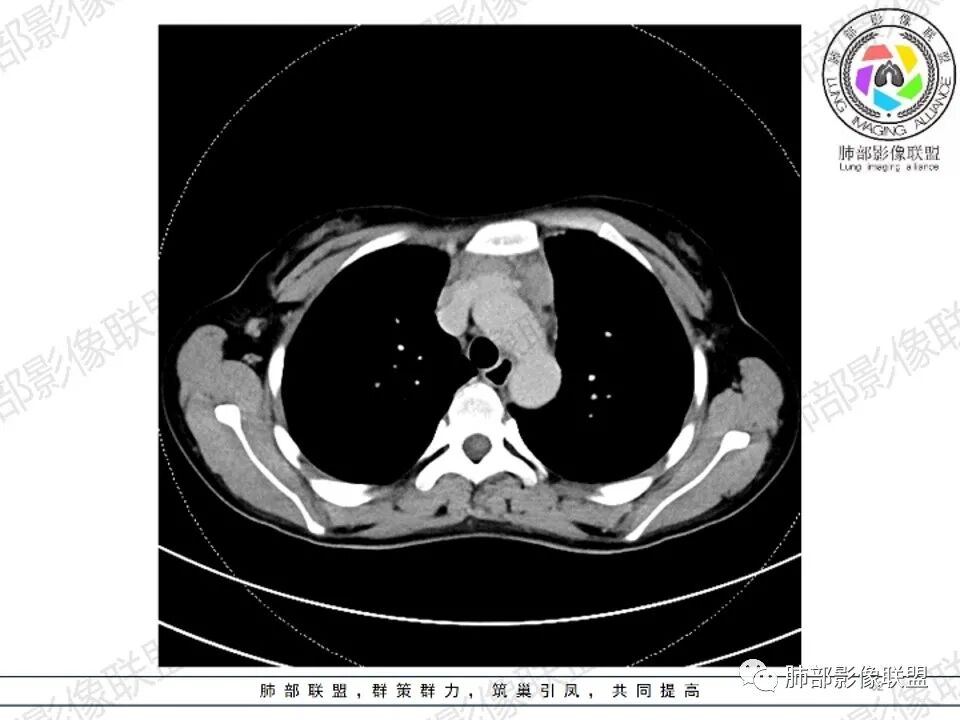

2.影像显示前纵隔不规则块状影,依势贴附心脏大血管旁,密度不均,边界不甚清楚,有结节融合感。

3.病灶轻度不均匀强化,可见血管穿行,散在液性低密度区。

双肺门未见肿大淋巴结。

4.双侧腋窝区见增大淋巴结,边界清楚。